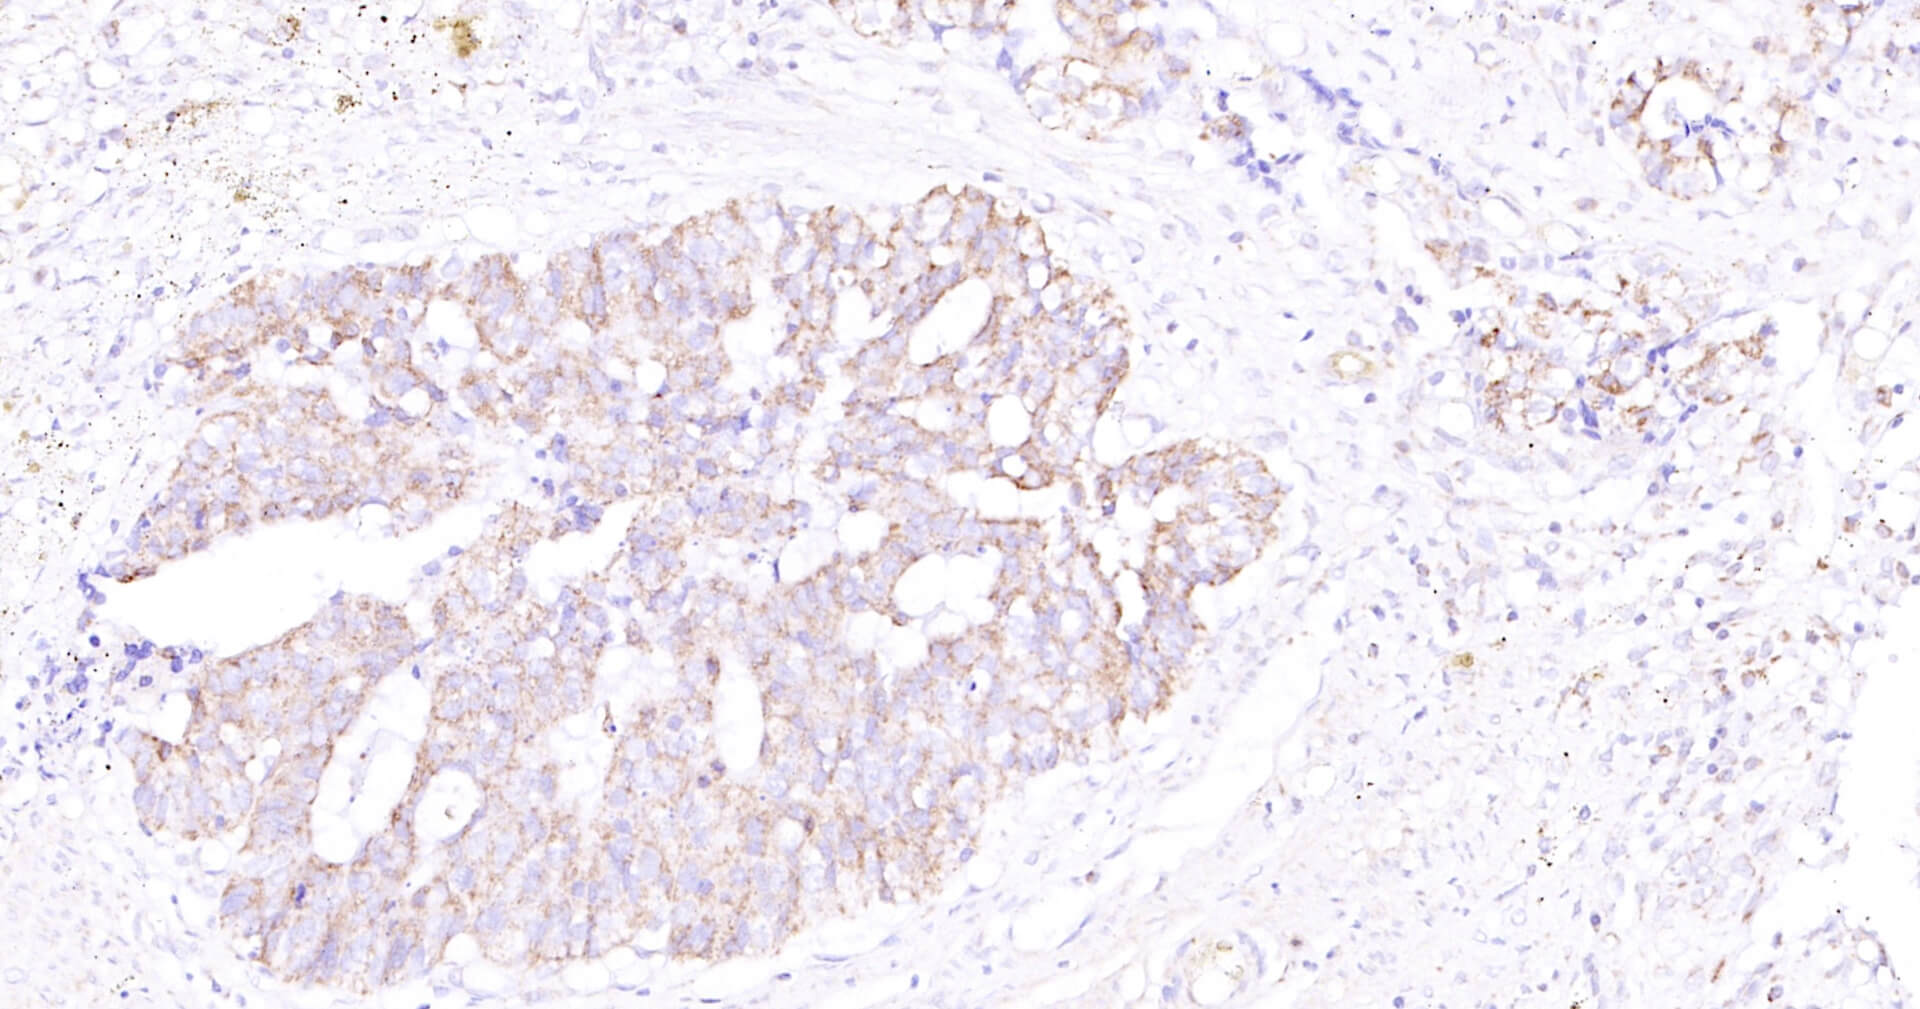

Immunohistochemical analysis of paraffin embedded human kidney tissue slide using IHC0131H (Human SLC44A1 IHC Kit).

Immunohistochemical analysis of paraffin embedded human brain tissue slide using IHC0131H (Human SLC44A1 IHC Kit).

Immunohistochemical analysis of paraffin embedded human colon carcinoma tissue slide using IHC0131H (Human SLC44A1 IHC Kit).

Immunohistochemical analysis of paraffin embedded human lung carcinoma tissue slide using IHC0131H (Human SLC44A1 IHC Kit).